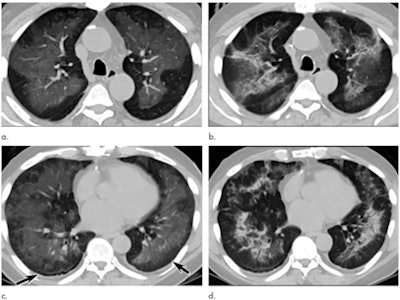

Gotway and colleagues investigated patterns on chest CT that might correspond to pathological findings for EVALI through a study that included 26 patients who met criteria for the condition and had undergone both CT as well as biopsy. The team classified CT findings as either ground-glass opacity or consolidation.

The most common CT finding among patients with EVALI also confirmed by pathology was multifocal or diffuse ground-glass opacity, identified in 96% of the study cohort -- a finding even more prevalent than that of subacute hypersensitivity pneumonitis, or lung tissue inflammation, according to the authors.